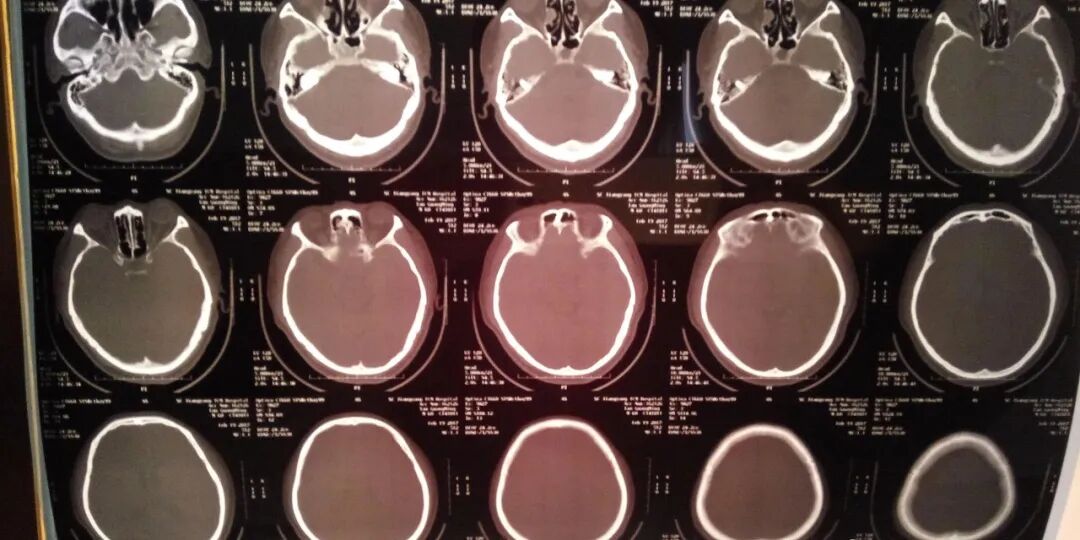

小脑萎缩是一种慢性神经系统疾病,表现为小脑体积缩小、神经元数量减少,并伴有平衡障碍、语言和步态异常等症状。虽然目前还没有完全治愈小脑萎缩的特异性治疗方法,但是中药治疗在此领域显示出一定的疗效和优势。本文将通过具体案例,探讨中药治疗小脑萎缩的临床效果。

患者李先生,68岁,退休工人。自述近年来行走不稳,言语不清,伴有记忆力减退等症状。经过一系列神经科检查,确诊为小脑萎缩。在进行了一段时间的西医治疗后,效果并不明显,于是寻求中医治疗。后来在短视频平台上看到了盛劲强大夫治疗小脑萎缩的效果不错,所以决定抱着试一试的心态找到了盛劲强大夫。

患者在服用中药两个疗程,行走不稳、语言不清等症状有所改善,但改善程度不大。继续服用至六个疗程,行走不稳症状明显减轻,语言不清症状改善显著。同时,患者精神状态也有所改善,生活质量得到提高。李先生为了巩固病情,还在继续治疗。